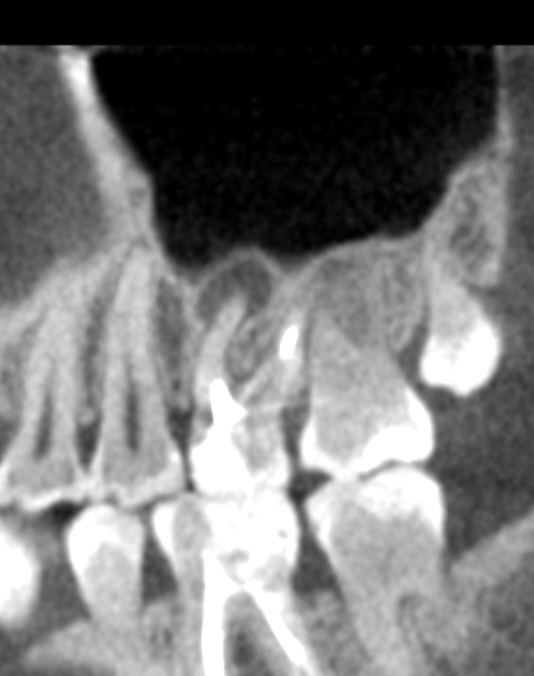

Киста на корне зуба размером 4 на 7 см. Компьютерная томография.

3. Это зона для ограниченного воспаления, где появляются кисты, иногда огромные полости с инфекционным субстратом. (См. изображение и комментарий стоматолога к нему).